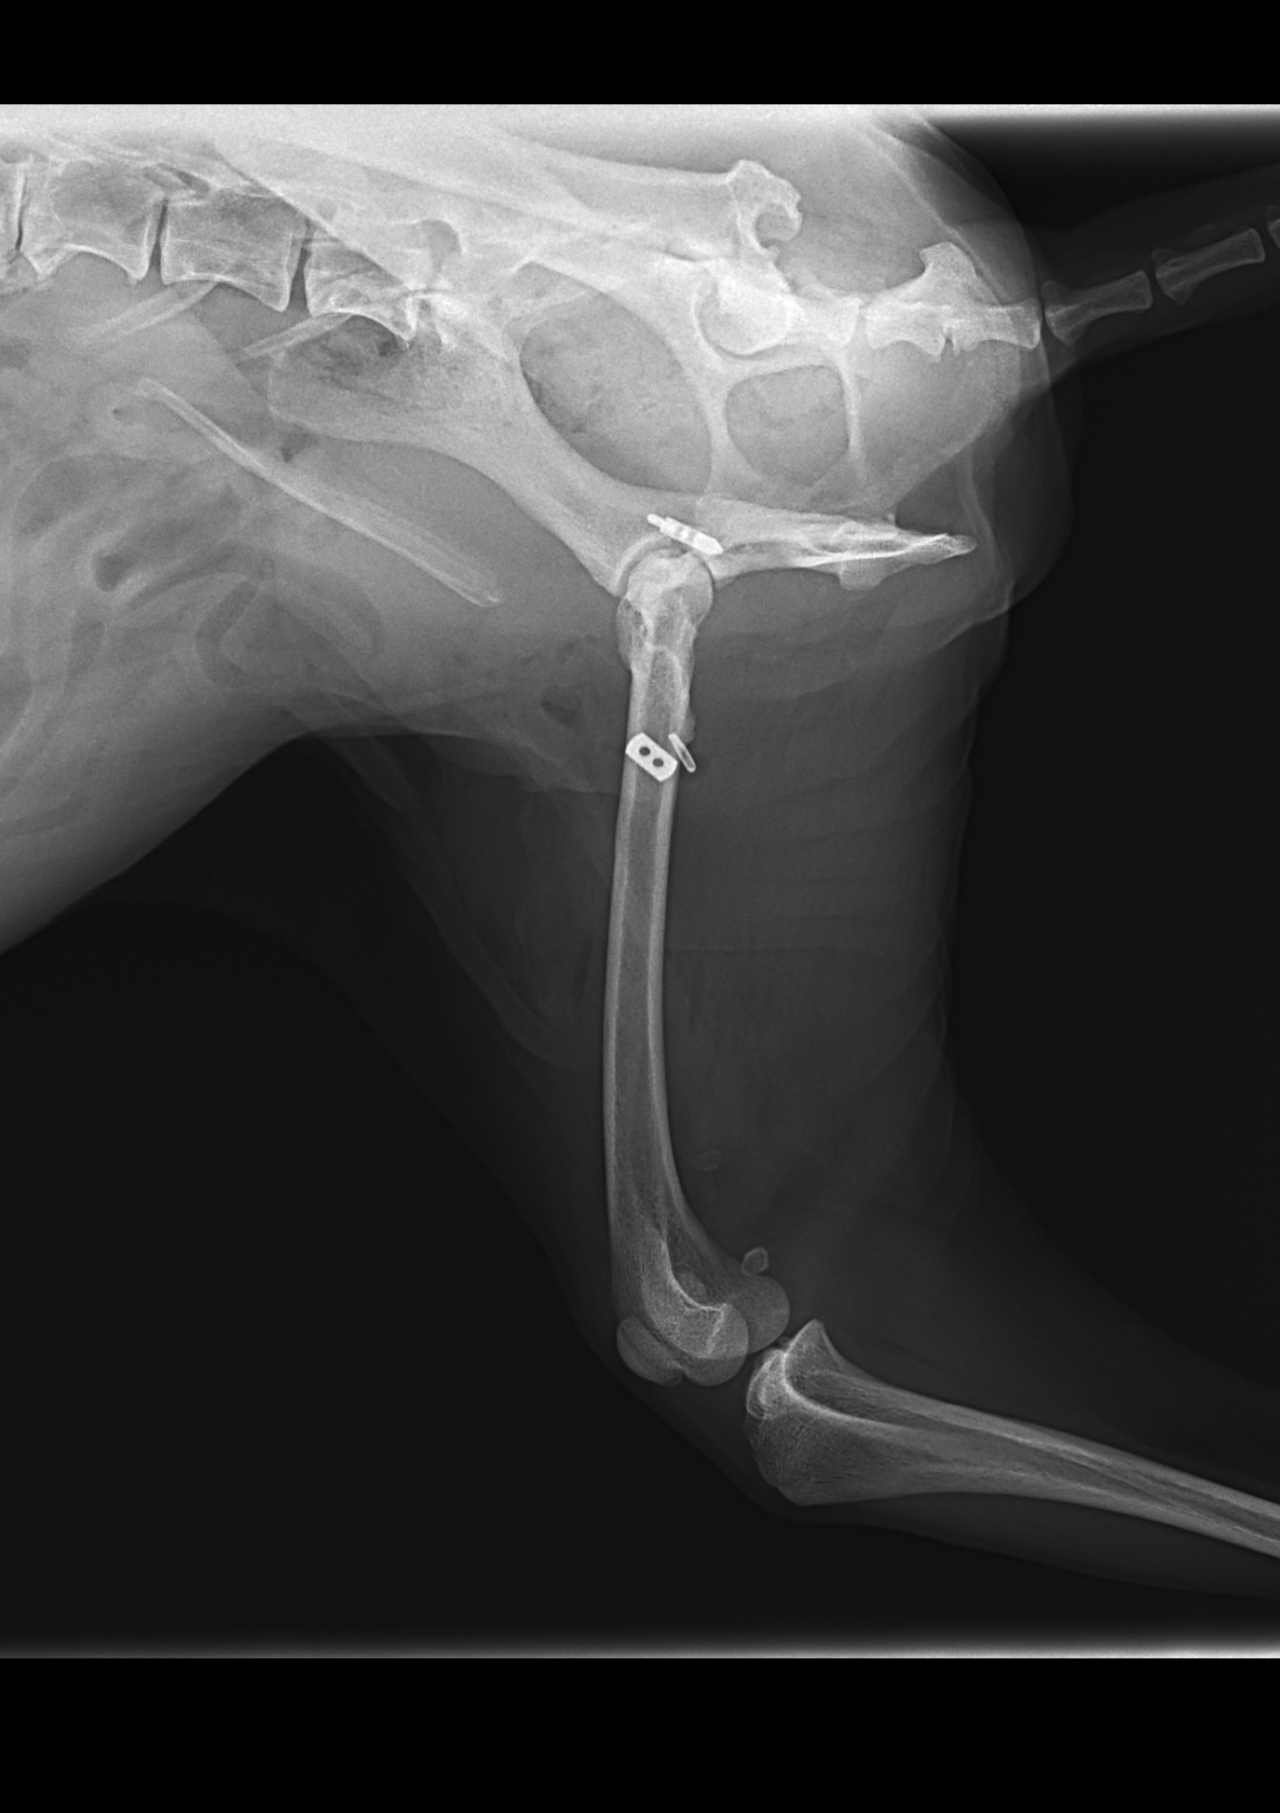

16歳のToy poodleさんが右の股関節を脱臼(背側前方)したとの事で主治医の先生から連絡がありました。1.9 Toggleとタイクロン(USP2)で整復術を実施しました。高齢ながら頑張ってくれました。2週間の安静期間が必要です。